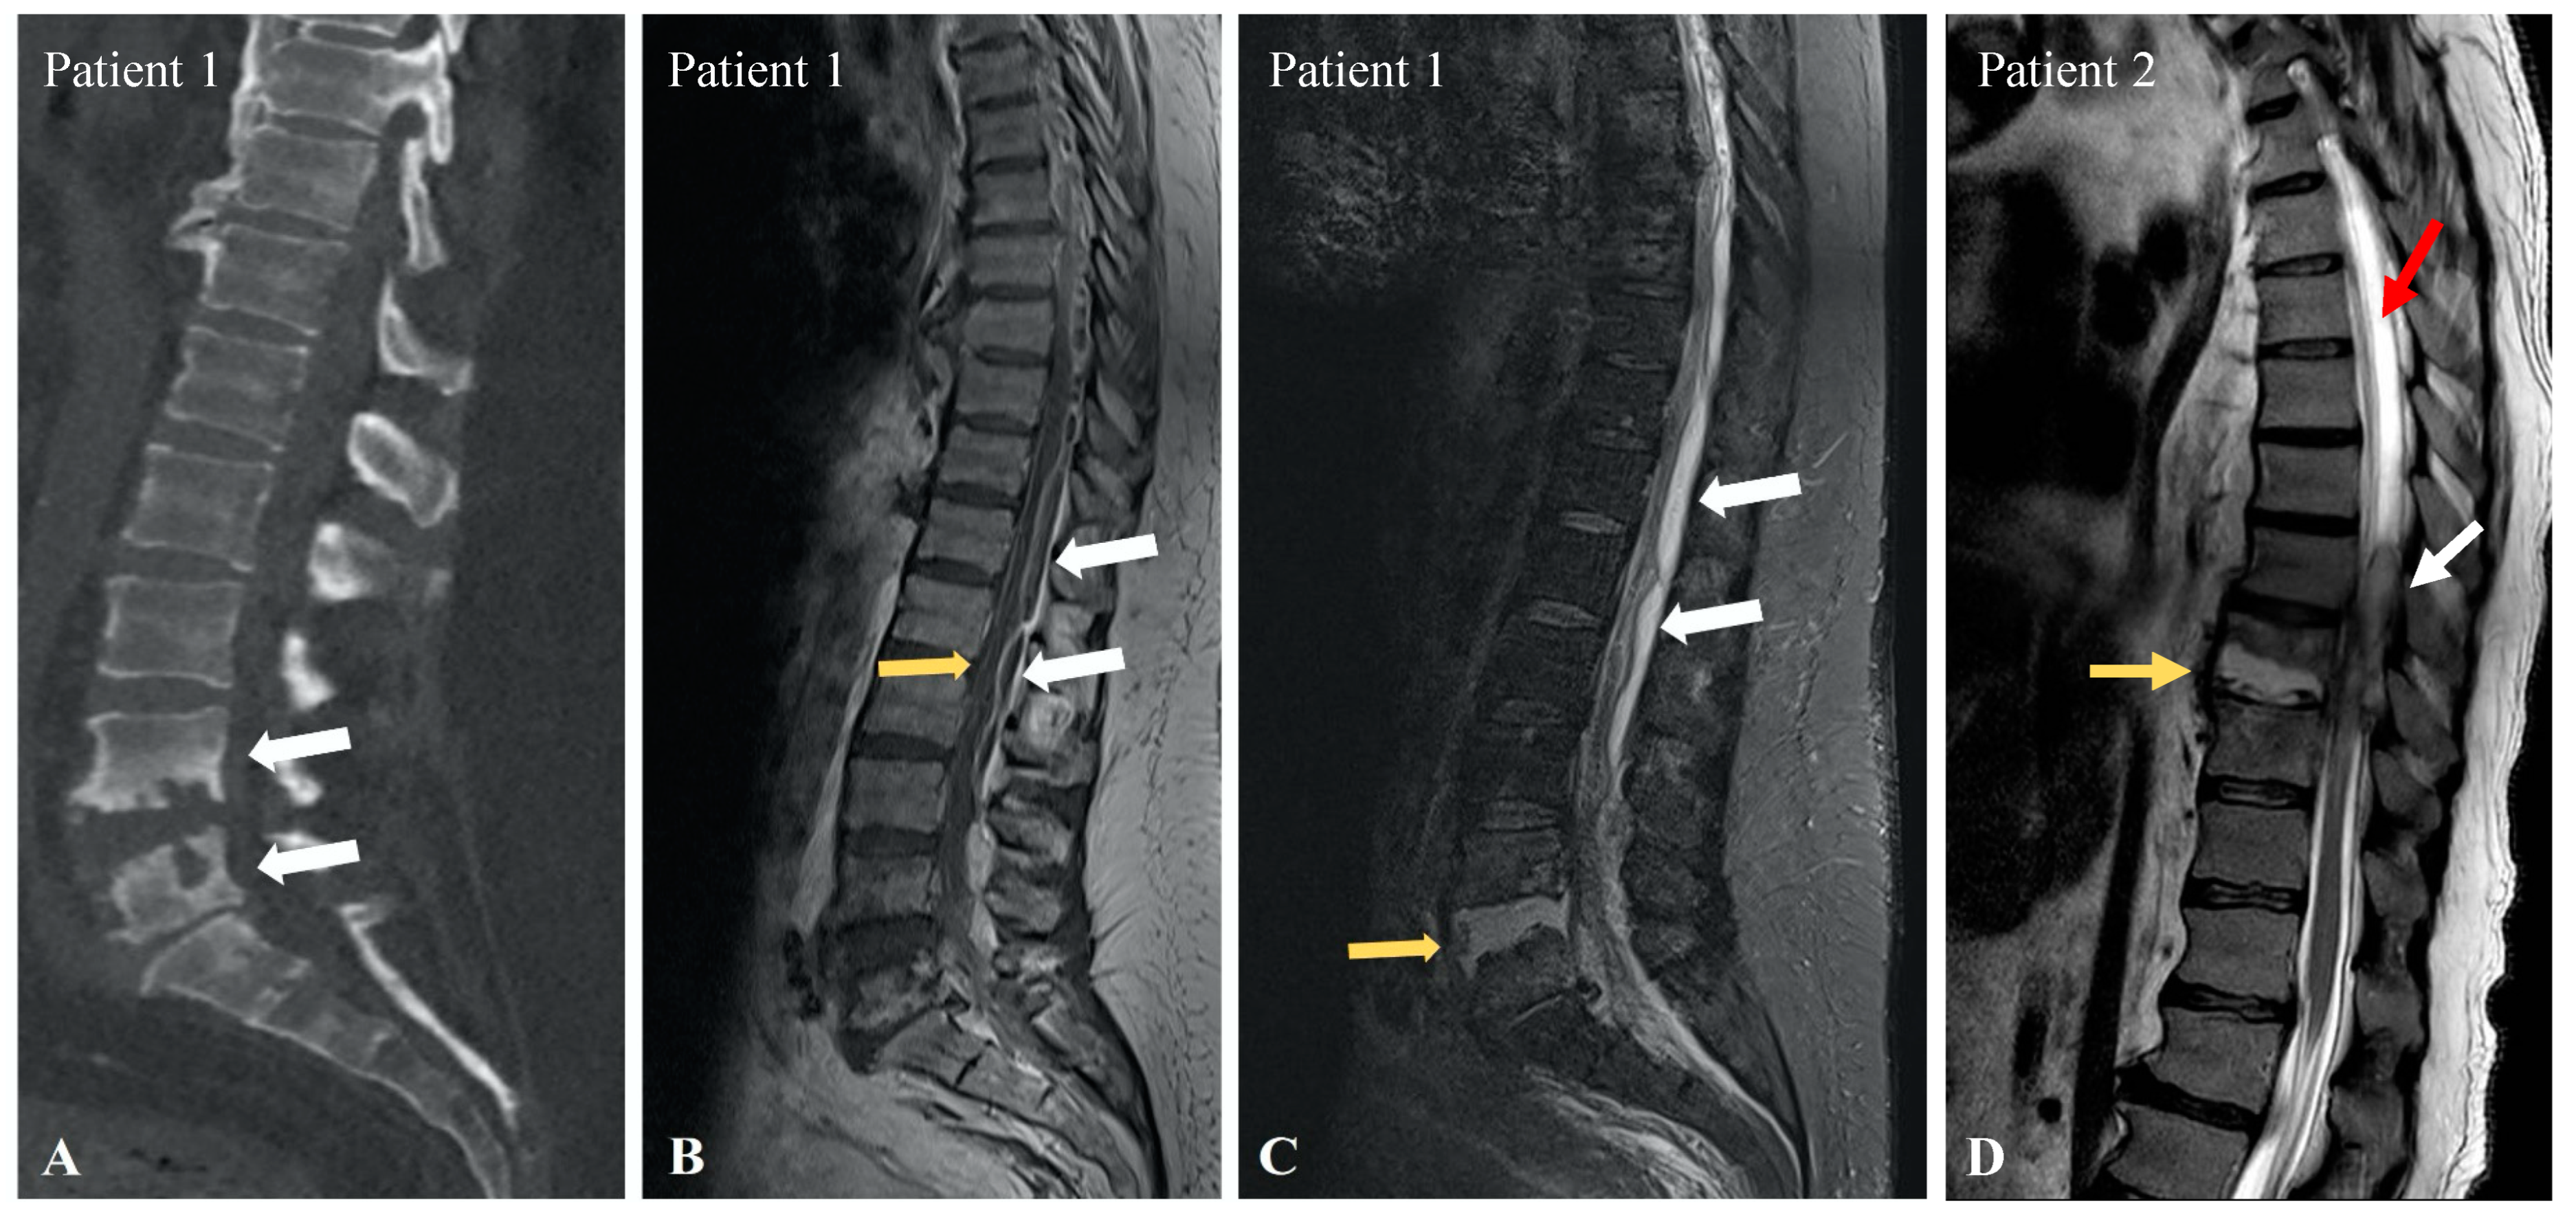

3.1. Patient 1